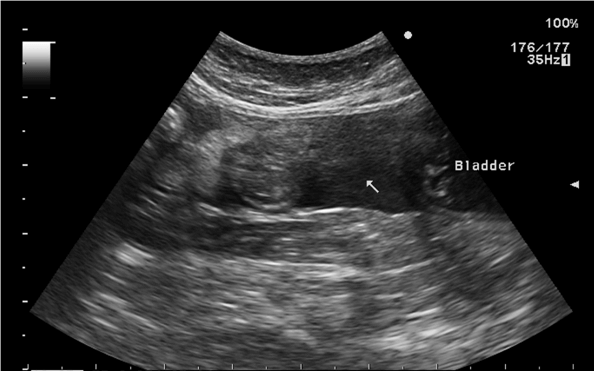

腹部超音波検査

― 右上腹部に40mm大の腫瘤陰影

― 腹腔内に液体貯留

― 穿刺吸引→血様の液体